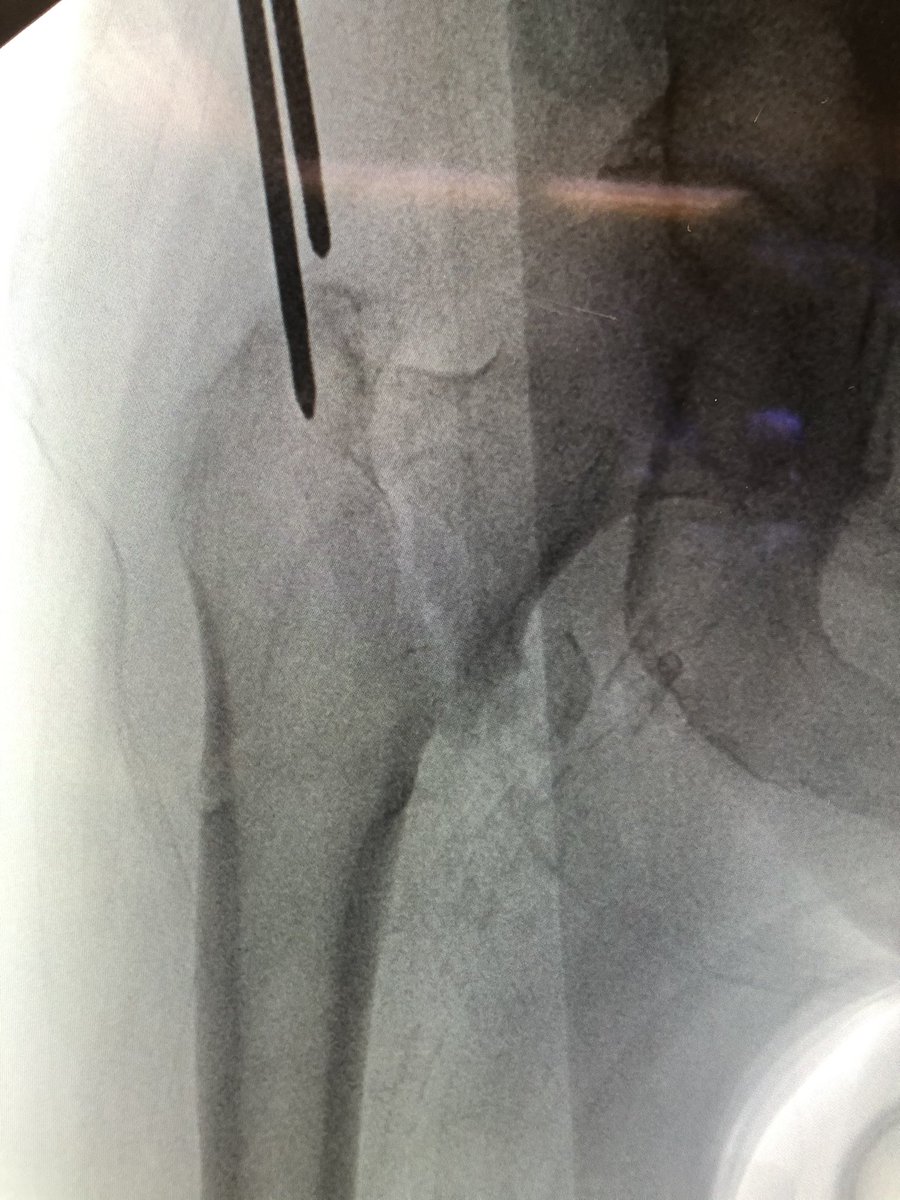

[14/18] If you line up screw handle with the line of the femur (blue) your screw end will be in the right plane. If it’s a left hip (clockwise screwing can flex the proximal fragment) I also build in an extra turn to derotate the proximal fragment if needed.

[15/18] I always try to build in some compression. The place to watch is the inferior medial portion of the fracture (arrow). Don’t overdo it or the nail starts to migrate medially.

[17/18] Before you remove jig, do a lateral and make sure distal screw is actually in the nail (blue). It seems impossible but I have seen it miss the nail. You don’t ever want to be cocky with trauma— just when you think you’re good enough to skip steps is when it humbles you.

[18/18] The troch fragment is little abducted here, I don’t worry so much about screw being close to fracture line because nails don’t rely on lateral wall to work. Keep TAD (or calTAD as I do) small and most ITs heal without an issue. I also don’t use blades. Thanks for reading!